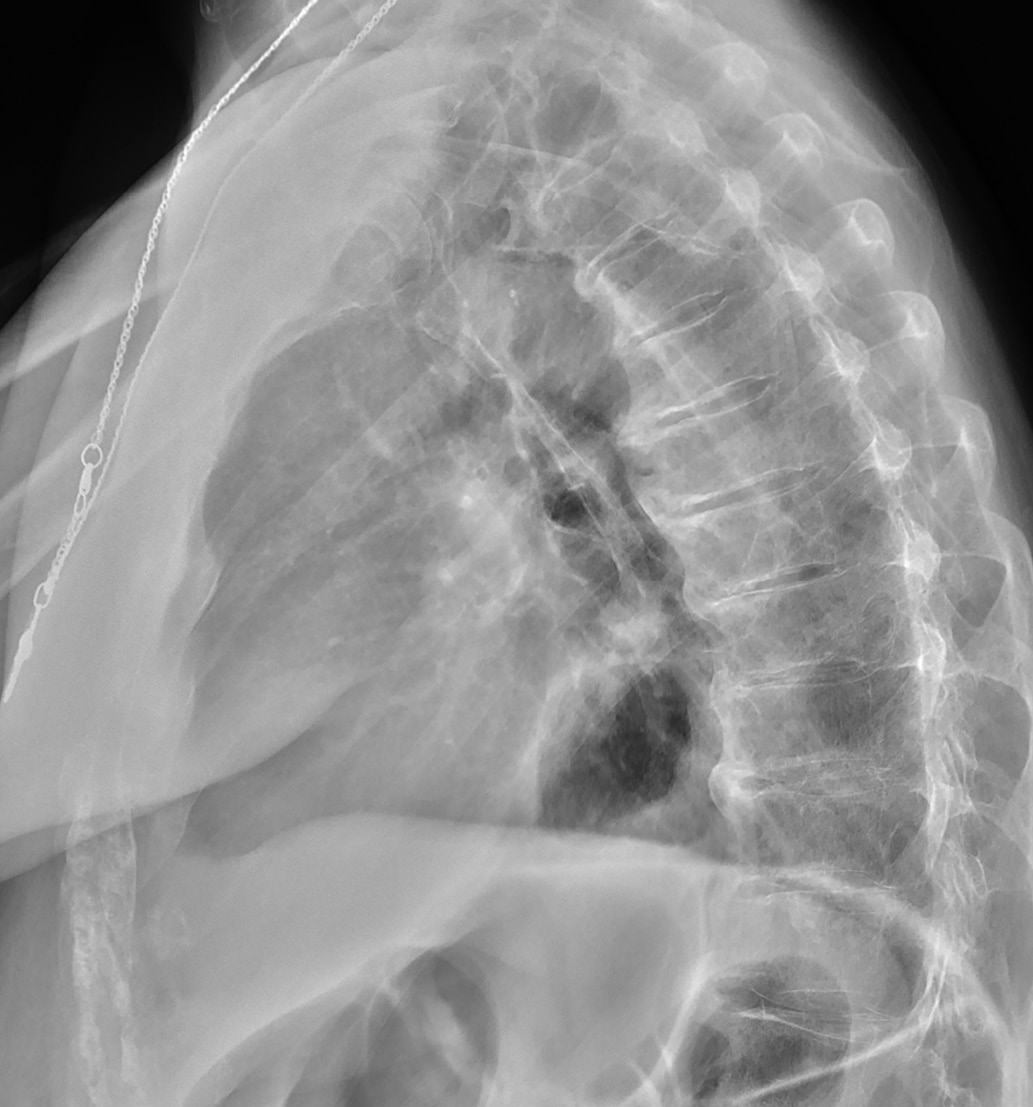

2. Fig. 2. Calcification of the anterior longitudinal ligament and reduction of disk space in a patient born in 1954 with acromegaly. | |